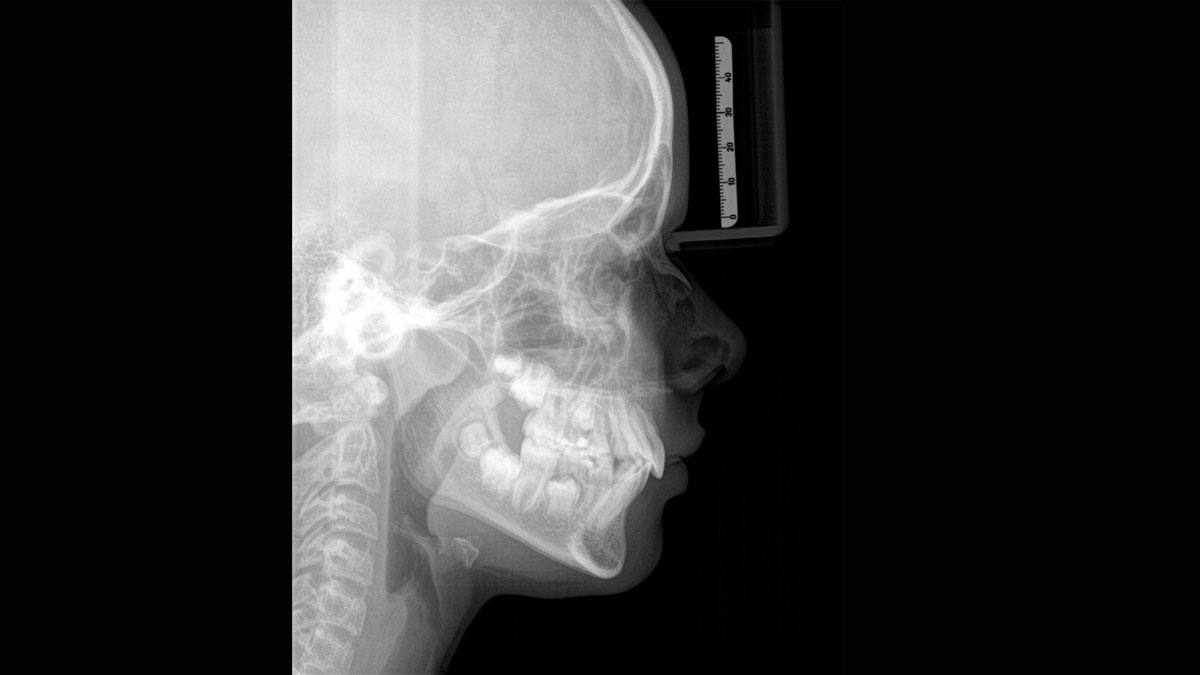

Der Autofokus erzeugt aus mehreren tausend Einzelbildern automatisch eine beeindruckende scharfe Panorama-Röntgenaufnahme

Eine Röntgenaufnahme muss sofort diagnostizierbar sein. Der Autofokus hilft dabei erheblich. Orthophos SL erfasst mehrere tausend Einzelbilder in einem Zyklus und erkennt automatisch scharfe Bereiche, um ein gleichmäßig scharfes Gesamtbild zu erzeugen. Der intelligente Autofokus erfordert keine manuellen Arbeitsschritte vor und nach der Erfassung.